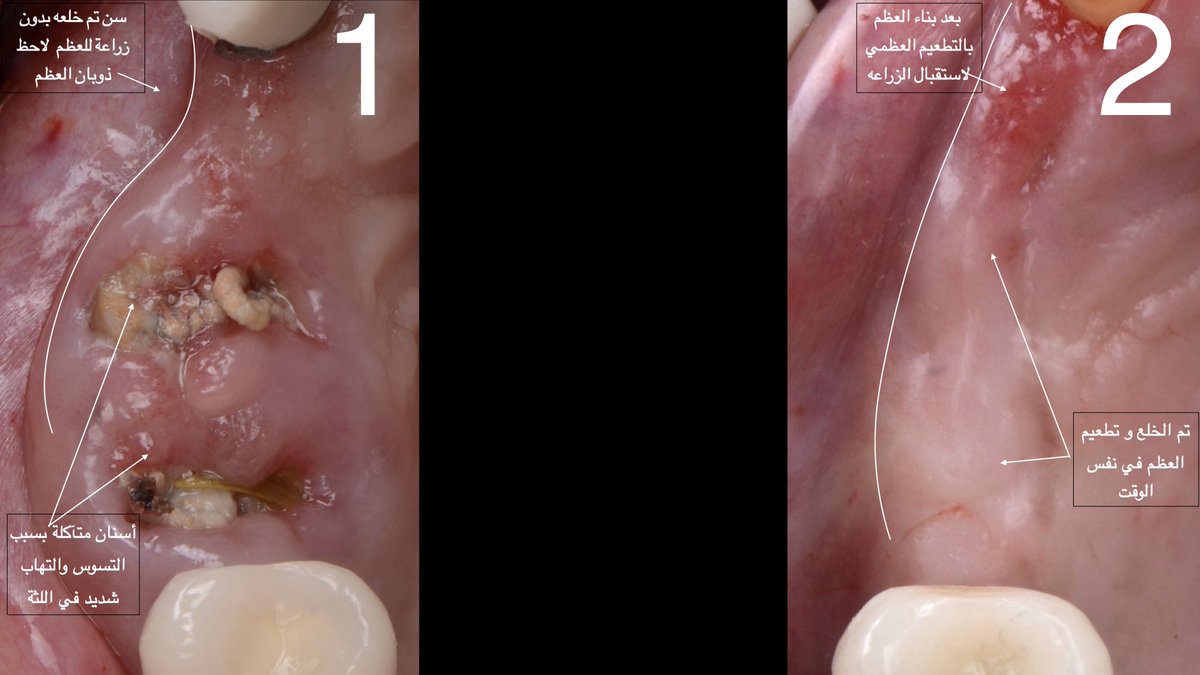

الهدف دائما الحفاظ على الأسنان،لكن بعض الحالات تصل فيها الأسنان لمرحلة صعب نحافظ عليها بسبب التسوس او لأسباب اخرى وعادة هذه الحالات تذهب الى الطواريء ويتم خلع الأسنان غالبا بدون أي أخذ في الاعتبار للخطة المستقبلية لتعويض السن،وهذا خطا شائع جدا وممكن يطيل مدة العلاج مستقبلا،لماذا؟

الجواب ، اولا بعد خلع السن يبدأ العظم في مكان الخلع بالإلتئام ولكن ينتج عنه ذوبان (تعبير مجازي) في العظم. يعني العظم يلتئم بس يكون حجمه اصغر. طيب ليه هذا الشيء مهم نعرفه؟، لان ذوبان العظم ممكن نتفاداه بطريقة جدا بسيطة وهي زراعة العظم (التطعيم العظمي) في نفس وقت الخلع،،، يتبع

وهذا يحافظ على كمية العظم الموجودة ويسهل عملية الزراعة مستقبلاً.